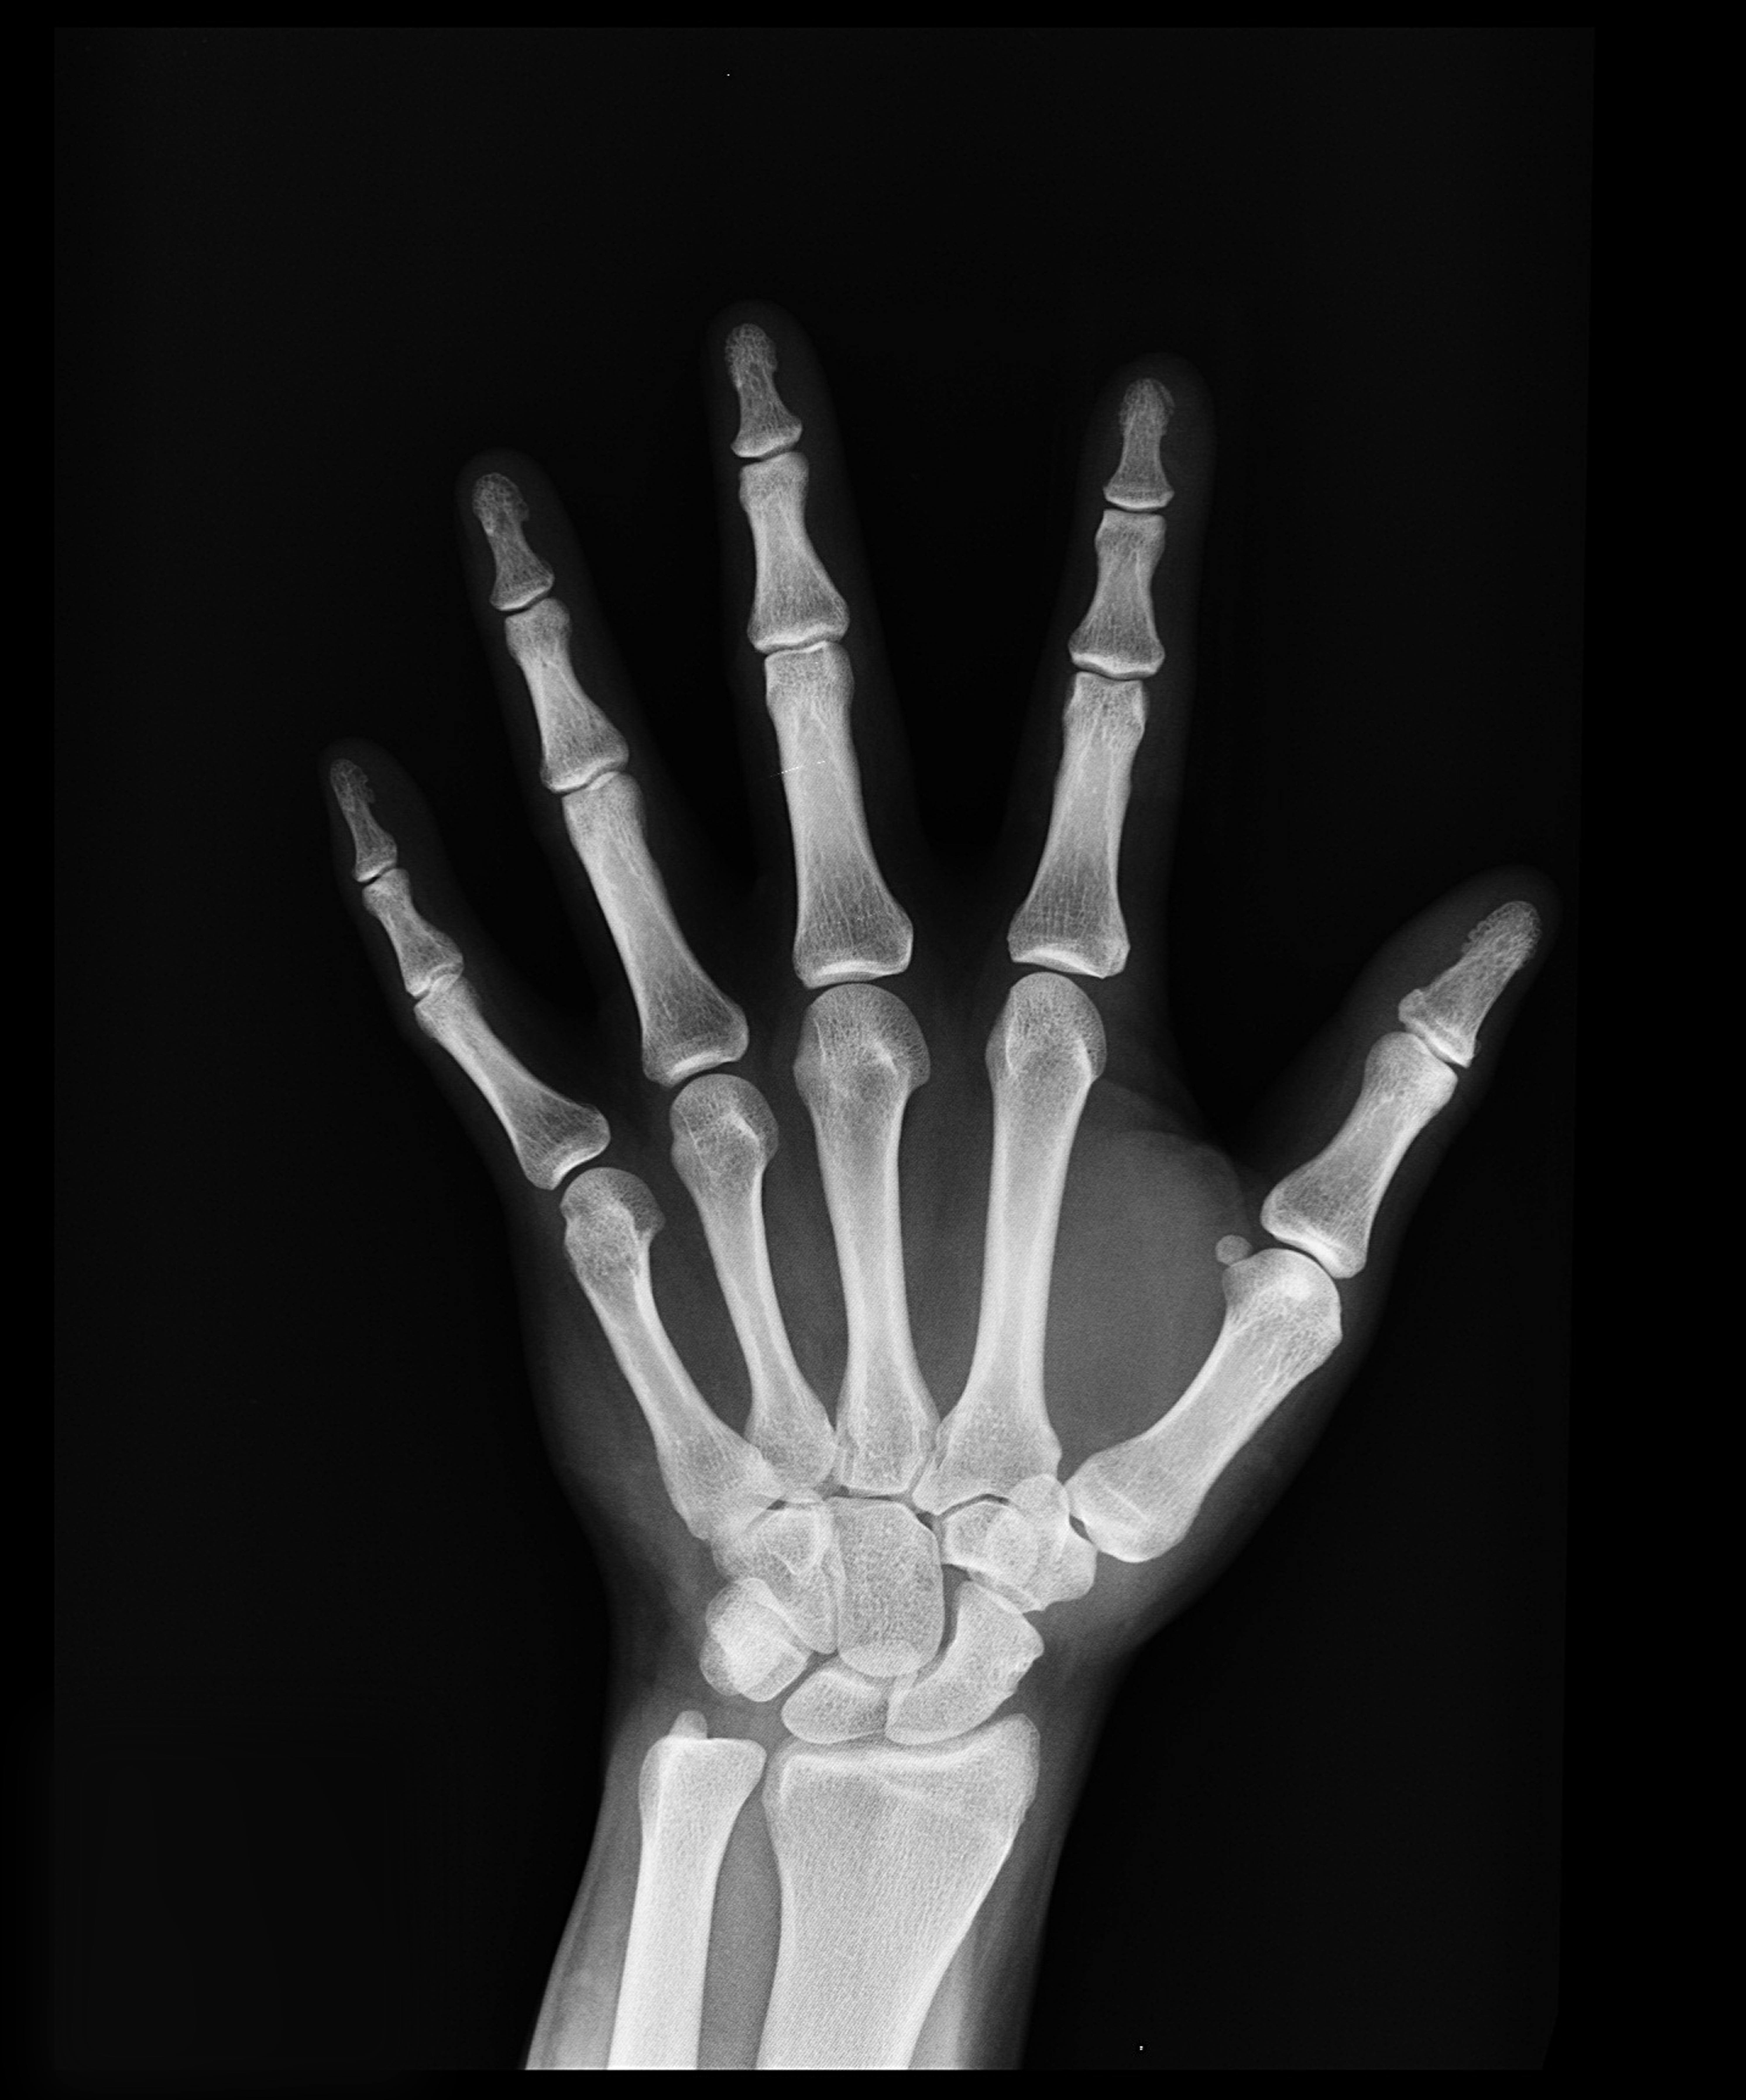

척추, 엉덩이, 손목, 갈비뼈 등 다양한 부위에서 골절이 쉽게 발생하며, 특히 척추압박골절은 키 감소와 만성 요통을 동반합니다.

| 손목 | 14% |

| 갈비뼈 | 7% |